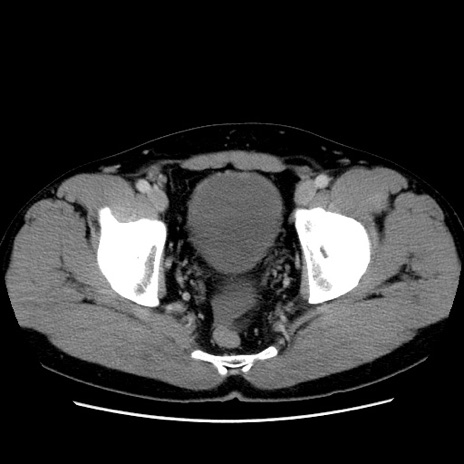

症例4(横断像)

【症例】30歳代男性

【主訴】腹痛、嘔吐

【現病歴】昨晩から突然の腹痛あり、その後嘔吐、軟便も出現。腹痛が改善しないため救急搬送となる。2日前にしめ鯖の食事歴あり。

【身体所見】意識清明、苦悶様、BP 135/90mmHg、BT 35.7℃、腹部:平坦、やや硬、心窩部〜臍部に自発痛、圧痛あり、筋性防御+、反跳痛-

【データ】WBC 8100、CRP 0.57